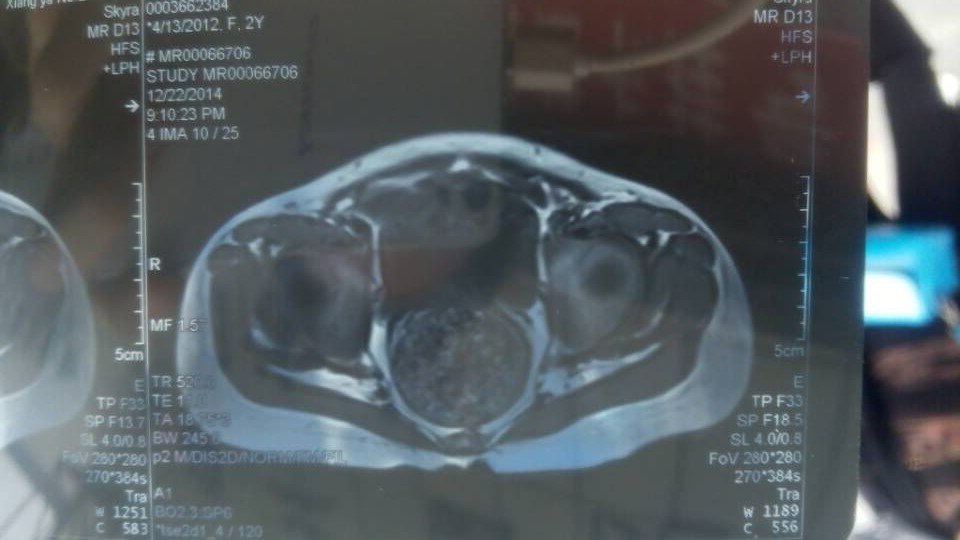

小孩摔了一跤走路一瘸一拐的,镇上怕CT说是两边不对称,怀疑有天生缺陷 刚做完核磁共振求诊断 点击展开 匿名用户 2014-12-23 14:46 为您推荐: 其他回答 这种情况的话,不排除是先天性的髋关节脱位的情况的,可以到骨科看看的,进行针对性的正畸治疗的。 知道张纪阳 2014-12-23 21:27 相关问题 两岁小孩突然走路一瘸一拐的,不痛不肿也不青,去了几家医院看了都说没事过几天就会好可过了半个多月了还 类似脑梗塞症状,但ct和核磁共振都显示不出 核磁共振和ct正常,脑供血不足怎么办